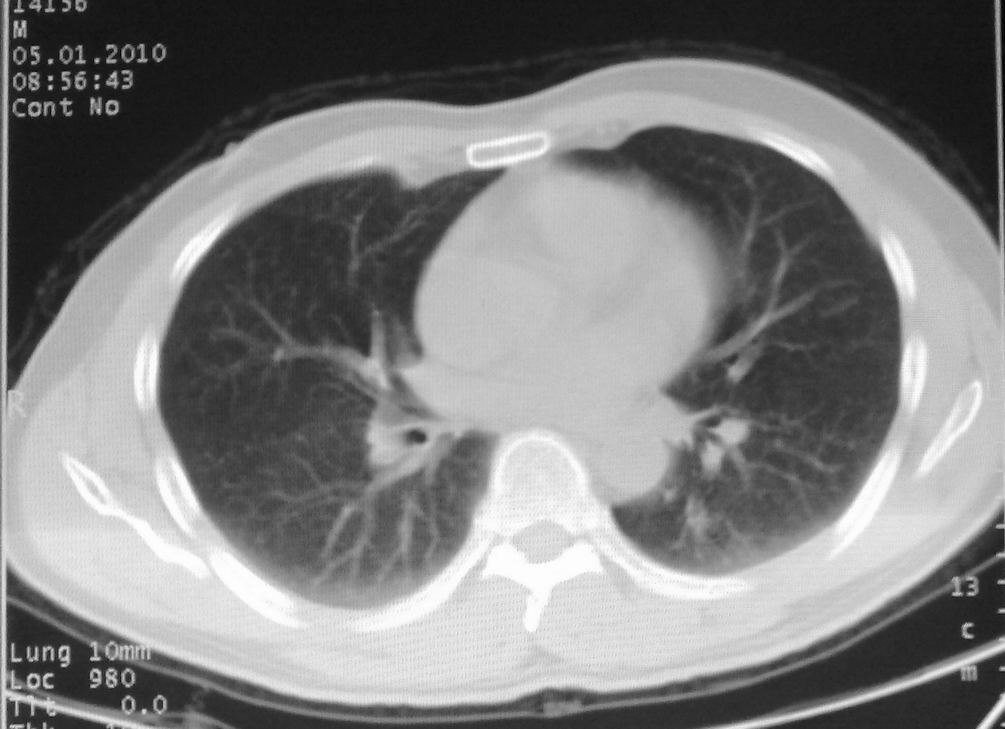

男,51岁,左胸前区不适数天。

薄壁空洞,边缘毛刺,胸膜凹陷,考虑肺癌,结核不排除。

考虑左肺下叶感染性病变。

考虑左肺下叶感染性病变。支持!建议查痰、hrct。

考虑左肺下叶感染性病变,不除外肺栓。